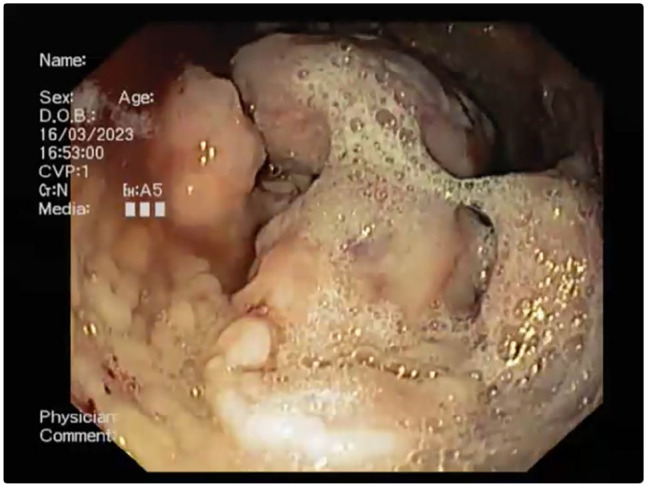

Case summary: This report describes a case of gastric mucormycosis in a young Ragdoll cat with a 5-day history of vomiting. Physical examination detected mild dehydration and tenderness was elicited on abdominal palpation. The results of blood work-up and radiographic study were unremarkable; however, abdominal ultrasonographic examination revealed multiple hyperechoic neoformations at the level of the pyloric antrum, which were confirmed on endoscopic examination. Non-septate hyphae of irregular diameter with a branched appearance were observed on cytology, and histological examination revealed severe diffuse necrotising and granulomatous gastritis with the presence of intralesional fungal hyphae indicative of mucormycosis, which was confirmed by PCR tests. Antifungal therapy with ketoconazole in addition to supportive treatment temporarily improved the clinical condition. Lethargy, fever and abdominal effusion developed in the following days. Cytological examination of abdominal fluid was compatible with septic peritonitis and, given the severity of the condition, euthanasia was opted by the owners. Post-mortem examination confirmed septic peritonitis resulting from perforation of the gastric wall at one of the neoformations of the pyloric antrum.

Relevance and novel information: To the authors' knowledge, this is the first reported case of gastric mucormycosis in a cat. Previous literature includes a case of mucormycosis in a Persian cat affecting only the duodenum. In both the Persian cat and the cat described here, gastrointestinal mucormycosis disease progressed rapidly and was fatal.